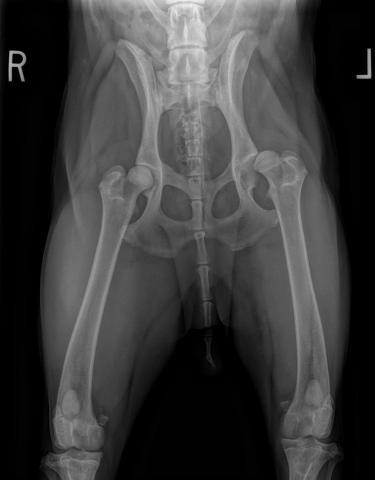

But when you need it the cat will provide it. A percentage of cats that take methimazole experience side effects including loss of appetite vomiting lethargy and occasionally blood cell abnormalities. The hip joint is made up of a ball and socket the ball being the head of the femur and the socket being the cup in the pelvis.

Hip dysplasia may occur at birth or develop in early life. If the ball femoral head is not held correctly in place the socket acetabulum may be more shallow than usual. Ultrasound and a state-of-the-art Toshiba 160 slice CT Scanner.

Hip dysplasia is where the head of the femur is an odd shape and does not fit in the socket perfectly. Willows is one of Europes leading small animal Orthopaedic referral centres treating over 1000 new patients a year. The onset of clinical signs is variable but hip dysplasia is most commonly diagnosed between 6 and 12 months of age.

Regardless it does not typically produce symptoms in babies less than a year old. Hip dysplasia abnormal development of the hip joints seen especially in Maine Coon cats but also Persians Siamese and other breeds Patella luxation dislocation of the kneecap which has been reported more commonly in Abyssinian and Devon Rex cats. Larger cat breeds are more prone to developing hip dysplasia than smaller cat breeds.

56 In females however the risk of developing hip dysplasia was higher for those spayed at. Hip dysplasia is the commonest orthopaedic condition in dogs. Although hip dysplasia might not be a massive issue for many cats the condition can cause arthritis which can be painful to your feline companion.